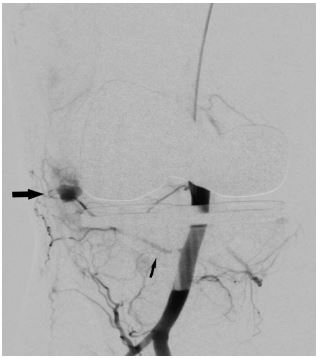

In view of continued knee joint swelling, the patient underwent right lower limb angiography the following week through the right femoral artery approach which identified a Pseudoaneurysm arising from the inferior medial genicular artery. This was embolized using 250 microns’ particles- embospheres and 2mm push able coils. Selective angiogram performed from superior medial and lateral genicular artery showed abnormal blush and pruning was done using 250-micron embospheres (Figures 3,4 & 5). An Ice pack was placed over the knee while instilling embolic agent particles to cause vasoconstriction of the skin arterial supply to avoid ischemia.

Figure 4: Post-operative Anteroposterior and lateral radiographs of Knee showing total knee replacement in place and gross joint eff usion in form of loss supra and infra patellar fat pad.